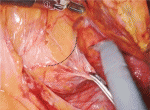

剥離面に十分に緊張がかからない場合は,助手によるカウンタートラクションが助けになる(図2).カウンタートラクションにより剥離面に緊張がかかり手術を円滑に進めることができる.また,助手による腹腔鏡用デバイスの使用(血管クリップ,ベッセルシーラー,自動縫合器等,図3,図4,図5,図6,図7)も,ロボット鉗子の交換時間が省け,手術時間の短縮に貢献できると考えている.ロボット鉗子の干渉により助手の操作制限をきたすことがあるが,その場合は術者がロボット鉗子位置を適宜調整し助手のワーキングスペースを確保する必要がある.体腔内再建時は,1本のロボット鉗子を抜去し助手ポートとして利用,助手が2本の鉗子を操作することも有用である(図8).